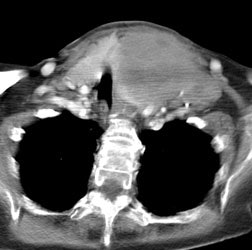

Hodgkins Lymphoma and Mastitis: The patient shown in the images below was a post-partum lactating female who presented for a baseline Ga-67 exam as part of her staging work-up for Hodgkins lymphoma (nodular sclerosing subtype). The planar whole body images demonstrate abnormal uptake of gallium within the patient's primary tumor in the mediastinum (blue arrow). Breast uptake is seen bilaterally (consistent with the patients history of lactation), but is asymmetric- right greater than left (red arrow). SPECT imaging was also performed (right). Asymmetric breast uptake was concerning for lymphomatous involvement of the breast, but on examination the patient was found to have a right breast mastitis. (Click images to enlarge) |